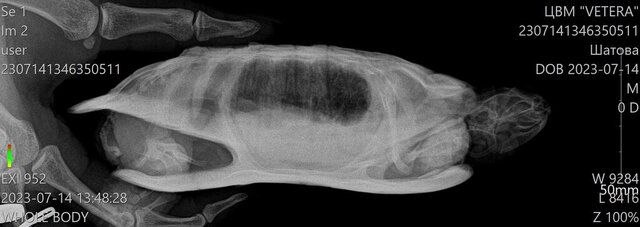

olga@ Ваше имя: Гоша Локация: Тульская область Опубликовано: 14 июля 2023 Автор Опубликовано: 14 июля 2023 (изменено) Рентген сделали в трёх проекциях, видимо мы не так поняли друг друга.Помогите пожалуйста, что нам дальше делать. Изменено 14 июля 2023 пользователем olga@

Консультанты moth Ваше имя: Мария Локация: Москва Опубликовано: 14 июля 2023 Консультанты Опубликовано: 14 июля 2023 @olga@ да, у неё проблемы с одним из лёгких. В норме на этой проекции оба лёгких выглядят как черная пустота (как в исходном примере №3), у Вашей одно лёгкое "мутное" - либо сдулось по какой-то причине, либо жидкость, пневмония и т.п. Здесь уже нужно врачу-герпетологу читать снимок и делать назначения, т.к. у консультантов нет для этого знаний. Это уже не форумный случай. По Туле у нас нет информации о хороших герпетологах, а наш врач, кто курирует форум, сейчас в отпуске на неделю (до понедельника). Могу Вам предложить либо написать её коллеге для онлайн консультации Ганькова Анастасия Сергеевна @Ansergan (ник в телеграмме) либо ещё онлайн консультирует Закружная Анжелика Дмитриевна https://t.me/anzhel_rept, но я не знаю какие у них цены за консультацию. Либо дождаться когда выйдет из отпуска наш врач, для форума у неё цена 300р за весь курс, оплата после консультации, но могут быть задержки в ответах сутки из-за высокой нагрузки. Черепаха сейчас продолжает нормально питаться?